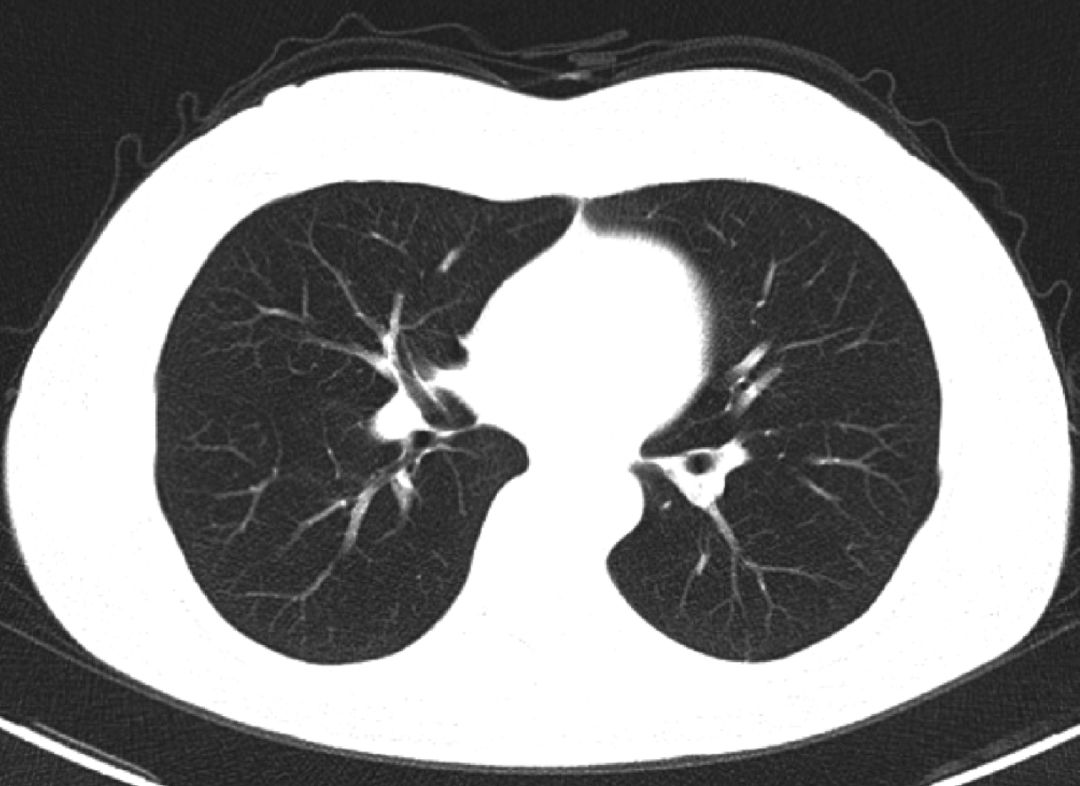

因“卵巢癌术后3 年余,下腹坠涨伴乏力半年余”于2016 年9 月初就诊于某三甲医院。患者于3 年前于外院行卵巢癌根治术,术后病检结果证实为卵巢来源子宫内膜样腺癌,术后予以紫杉醇+顺铂方案化疗8 个周期,化疗期间定期复查未见肿瘤复发及远处转移。近半年来,患者自觉下腹坠涨,久坐或排大便时自觉坠涨感加强就诊,胸部CT 检查未见异常(图1)。上腹部及盆腔MRI 检查(图2、图3):肝脏多发占位、腹壁异常占位及盆腔直肠区域异常占位,结合病史考虑患者为卵巢癌术后盆腔复发侵犯直肠,同时并肝脏多发转移。余影像检查无明显异常。

图1 肺部CT检查结果